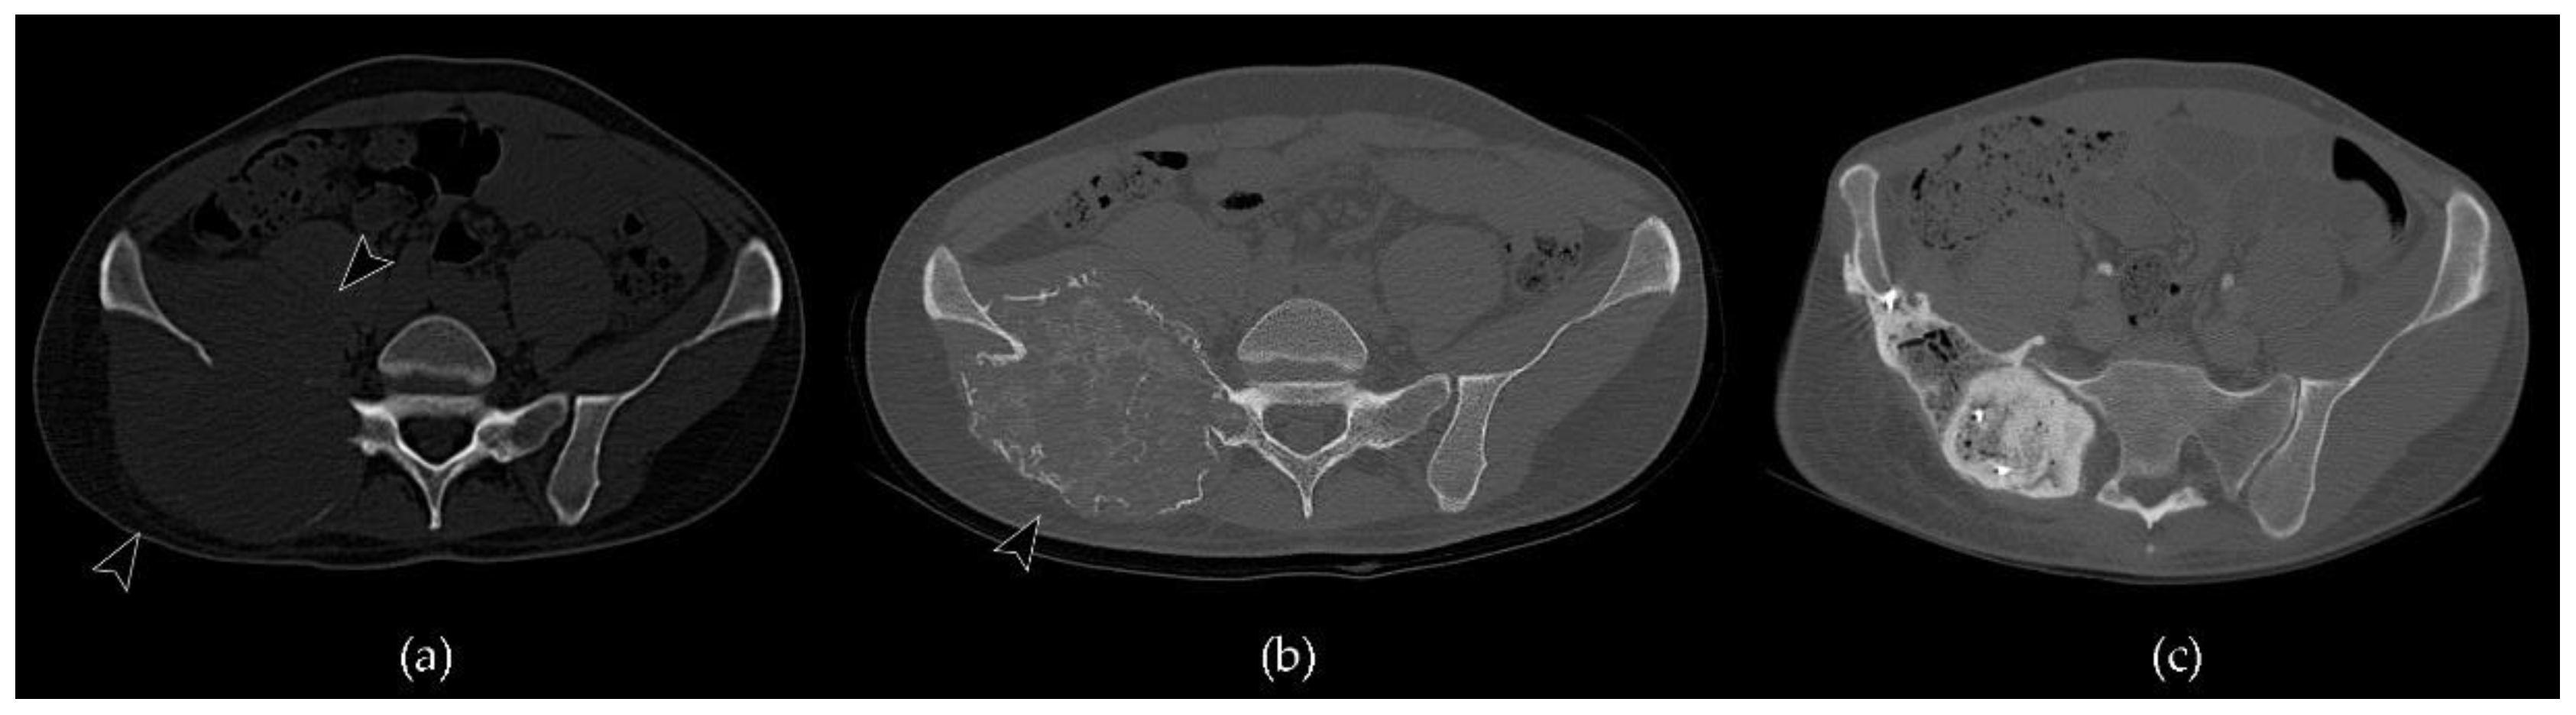

- Murphey, M.D.; Nomikos, G.C.; Flemming, D.J.; Gannon, F.H.; Temple, H.T.; Kransdorf, M.J. From the archives of the AFIP. Imaging of giant cell tumor and giant cell reparative granuloma of bone: Radiologie-pathologic correlation. Radiographics 2001, 21, 1283–1309. [Google Scholar] [CrossRef] [PubMed]

- Chakarun, C.J.; Forrester, D.M.; Gottsegen, C.J.; Patel, D.B.; White, E.A.; Matcuk, G.R. Giant cell tumor of bone: Review, mimics, and new developments in treatment. Radiographics 2013, 33, 197–211. [Google Scholar] [CrossRef]

- Baumgartner, K.; Haap, M.; Bösmüller, H.; Horger, M. Imaging of giant cell tumors of the bone, RoFo Fortschritte Auf Dem Gebiet Der Rontgenstrahlen Und Der Bildgeb. Verfahren 2020, 193. [Google Scholar] [CrossRef]

- Campanacci, M.; Baldini, N.; Boriani, S.; Sudanese, A. Giant-cell tumor of bone. J. Bone Jt. Surg. Ser. A 1987, 69, 106–114. [Google Scholar] [CrossRef]

- van Langevelde, K.; van Vucht, N.; Tsukamoto, S.; Mavrogenis, A.F.; Errani, C. Radiological Assessment of Giant Cell Tumour of Bone in the Sacrum: From Diagnosis to Treatment Response Evaluation. Curr. Med. Imaging Former. Curr. Med. Imaging Rev. 2021, 17. [Google Scholar] [CrossRef] [PubMed]